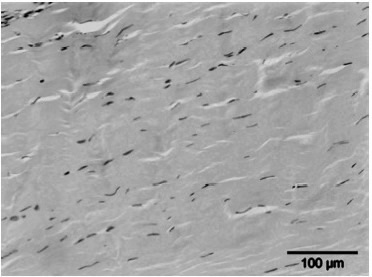

• Het stimuleren van de collageenproductie en het afvoeren van beschadigd collageen, wat resulteert in een verhoogde matrix-turnover.

Een tweede hypothese is dat ESWT een positief effect heeft op weefselregeneratie door:

• De toename van neovascularisatie in de pees-bot overgang.

•  Het opwekken van groeifactoren zoals vasculo-endothelial growth factor (vegf).

• Het beïnvloeden van stamcelmigratie en -proliferatie via mechanotransductie.

• De stijging in de celpermeabiliteit. De stimulatie van de celdeling.